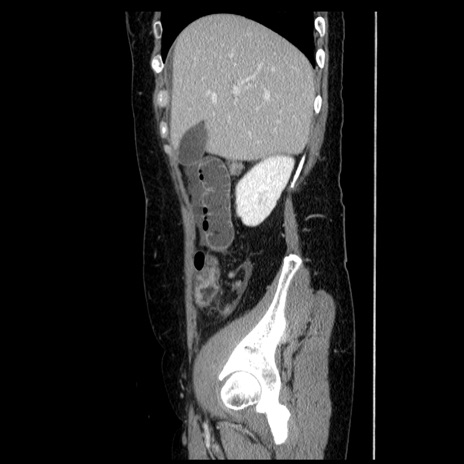

症例6(矢状断像)

【症例】50歳代女性

【主訴】下腹部痛

【現病歴】本日朝より下痢2回あり。 昼食を食べた後、嘔吐3回、下腹部痛認め、症状軽快せず、当院救急搬送。

最終食事:本日昼(生ものなし)。 昨日の夜、刺身を食ぺたとのこと。周囲に同様の症状の者なし。普段、排便は毎日あるとのこと。

【既往歴】卵巣癌術後(8年前に当院で卵巣摘出)

【身体所見】 意識清明、腹部:平坦、腸蠕動音→、やや硬、下腹部自発痛・圧痛あり、反跳痛あり、筋性防御なし。

【データ】WBC 16000、CRP 0.01